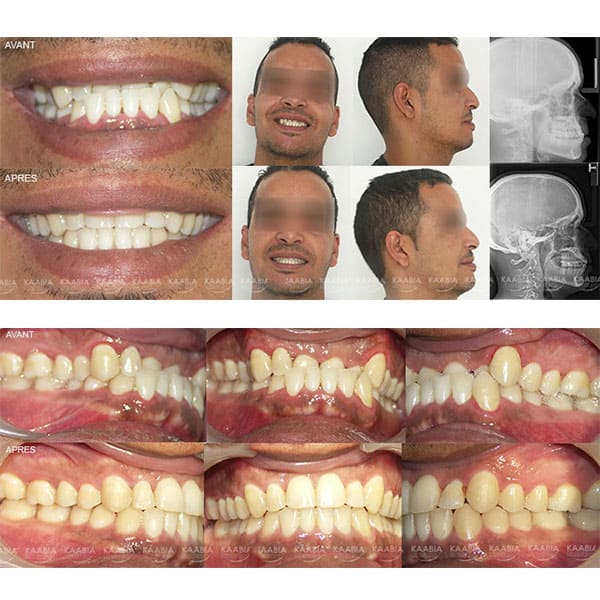

Traitement sans extraction_ri

Traitement des retroalvéolies inférieurs